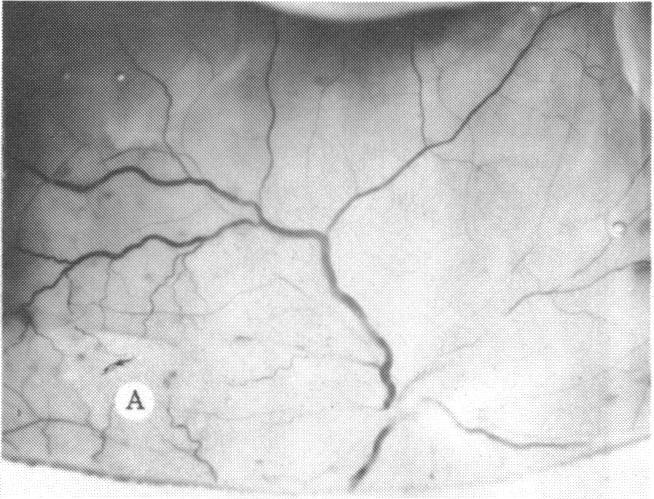

The clinical and histopathologic features of 29 eyes from 29 patients with central retinal vein occlusion (CRVO) are reported. A fresh or a recanalized thrombus was observed in each eye. This study considers the temporal aspects of the cases, and it notes the different morphologic features of the occlusion. These observations explain most of the variability of the changes observed in previous reports. We believe that these different features represent the various stages in the natural evolution of such a thrombus. The interval between CRVO and histopathologic study in our series ranged from six hours to more than 10 years. Local and systemic factors were reviewed and were found to be important in the pathogenesis of thrombus formation. Local diseases with a predisposing effect on CRVO included: glaucoma, papilledema, subdural hemorrhage, optic nerve hemorrhage, and drusen of the optic nerve head. Associated systemic diseases included: hypertension, cardiovascular and cerebrovascular disease, diabetes mellitus, and leukemia with thrombocytopenia. A fresh thrombus in the CRVO was observed in three (10.3%), and a recanalized thrombus in 26 eyes (89.7%). Endothelial-cell proliferation was a conspicuous feature in 14 (48.3%) of the eyes. Chronic inflammation in the area of the thrombus, and/or vein wall or perivenular area was observed in 14 (48.3%) of the eyes. Arterial occlusive disease was observed in seven eyes (24.6%). Cystoid macular edema was found in 26 (89.7%) of the eyes.

报告了29例视网膜中央静脉阻塞(CRVO)患者29只眼的临床和组织病理学特征。每只眼中均观察到新鲜或再通的血栓。本研究考虑了病例的时间因素,并记录了阻塞的不同形态学特征。这些观察结果解释了先前报告中观察到的变化的大部分变异性。我们认为这些不同特征代表了此类血栓自然演变的各个阶段。我们系列中CRVO与组织病理学研究之间的间隔时间从6小时到10多年不等。对局部和全身因素进行了回顾,发现它们在血栓形成的发病机制中很重要。对CRVO有 predisposing 作用的局部疾病包括:青光眼、视乳头水肿、硬膜下出血、视神经出血和视神经乳头玻璃膜疣。相关的全身疾病包括:高血压、心血管和脑血管疾病、糖尿病以及伴有血小板减少的白血病。在CRVO中观察到3只眼(10.3%)有新鲜血栓,26只眼(89.7%)有再通血栓。14只眼(48.3%)中内皮细胞增殖是一个显著特征。14只眼(48.3%)中观察到血栓区域、和/或静脉壁或静脉周围区域有慢性炎症。7只眼(24.6%)中观察到动脉闭塞性疾病。26只眼(89.7%)中发现黄斑囊样水肿。 (注:文中“predisposing”可能是“易患的”意思,但在专业医学语境中,可能有更准确特定含义,这里按常见理解翻译,具体含义需结合医学专业知识进一步确认。)